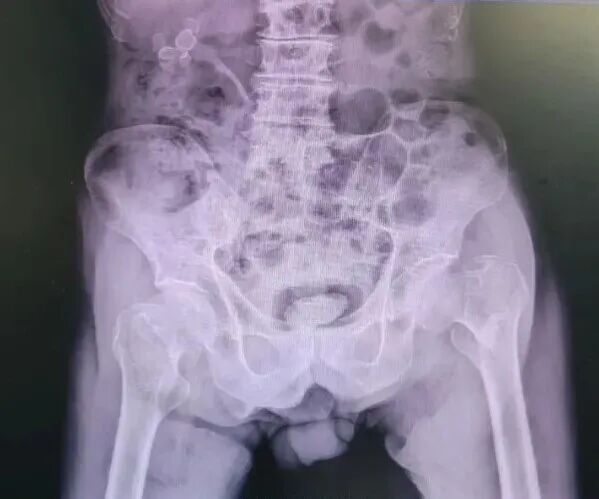

年近百岁的梁老伯,身体本就患有高血压、冠心病、慢性心力衰竭、慢性阻塞性肺疾病伴感染、贫血等多种基础疾病,身体机能薄弱。此次在家中意外摔倒后,被确诊为股骨颈-粗隆间骨折,疼痛难忍无法下床,生活完全不能自理。面对超高龄与复杂基础病的双重挑战,家属对手术治疗充满顾虑,却又抱着一丝希望,将老人送至我院骨科。

老年人髋部骨折被称为“人生最后一次骨折”,它包括股骨颈骨折、股骨粗隆间骨折,多发生于平均年龄在70岁左右的老年人,此类患者常合并多种内科疾病,如不及时处理,原发疾病会随之加重,且较难控制直至危及生命。国外研究统计,由于以上种种原因,老年人发生髋部骨折后,一年生存率只有50%。